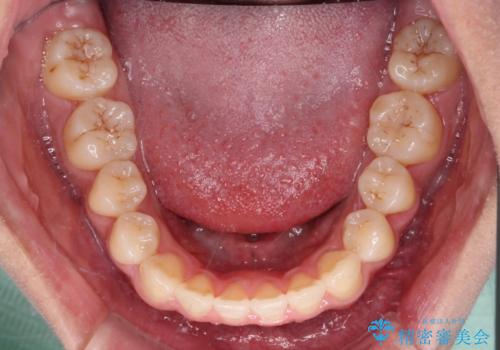

上顎骨を拡大することで、八重歯やデコボコを歯列に収めることができ、下顎の歯が外に位置していた奥歯の咬み合わせも改善することができました。

スペースも短期間に獲得できるため、1年程度で治療を終えることができました。